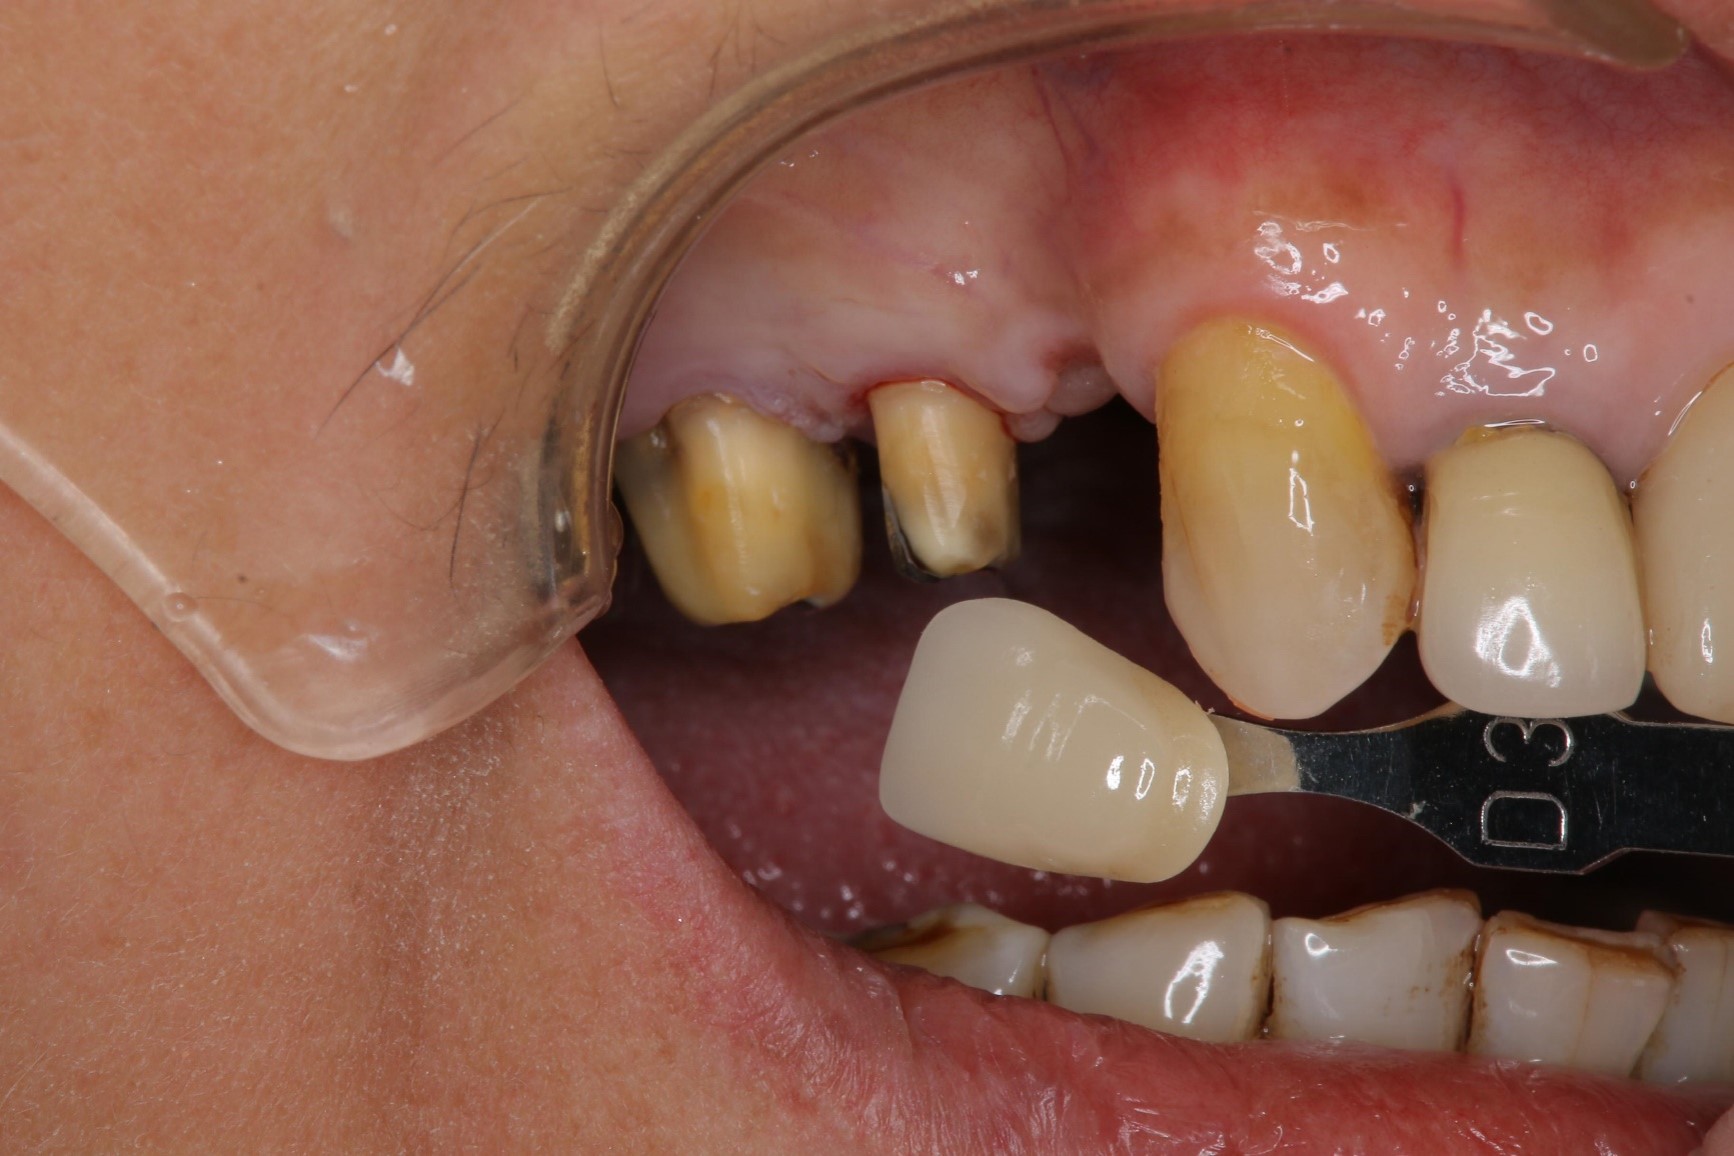

膺復前評估牙齦、牙齒狀態

照相比色